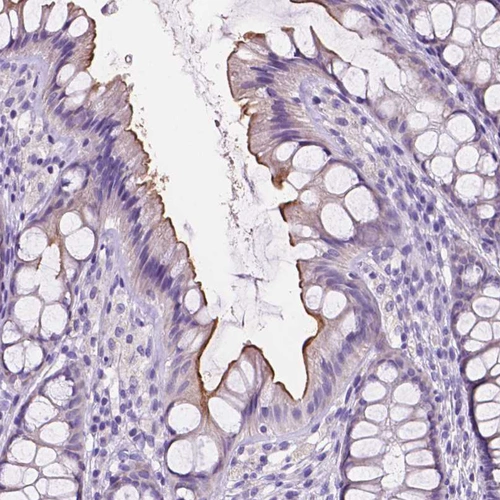

Immunohistochemical staining of human lower colon shows moderate cytoplasmic-membranous positivity in glandular cells.